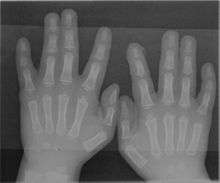

A finger is a limb of the human body and a type of digit, an organ of manipulation and sensation found in the hands of humans and other primates.[1][2] Normally humans have five digits, the bones of which are termed phalanges,[2] on each hand, although some people have more or fewer than five due to congenital disorders such as polydactyly or oligodactyly, or accidental or medical amputations. The first digit is the thumb, followed by index finger, middle finger, ring finger, and little finger or pinky. According to different definitions, the thumb can be called a finger, or not.

A rare anatomical variation affects 1 in 500 humans, in which the individual has more than the usual number of digits; this is known as polydactyly. A human may also be born without one or more fingers or underdevelopment of some fingers such as symbrachydactyly. Extra fingers can be functional. One individual with seven fingers not only used them but claimed that they "gave him some advantages in playing the piano".[13]